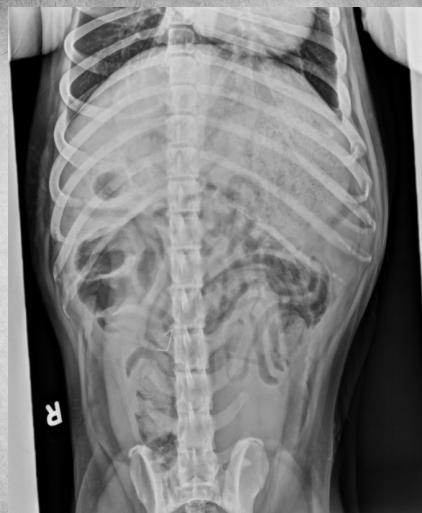

●6 mo female Great Dane

●Vomiting, loss of appetite for 3 days

●Suspected foreign body

● Entire small intestine moderately homogenously fluid filled, teeny bubbles throughout GI tract indicating GI hypomotility.

● Markedly gas-distended intestinal segment in mid-abdomen, reverse C-shaped, most likely normal caecum.

● Diffusedly fluid filled GIT with interspersed gas bubbles is most consistent with functional ileus from severe enteritis.

● No radiographically evident foreign body.

● Dx: Parvoviral enteritis